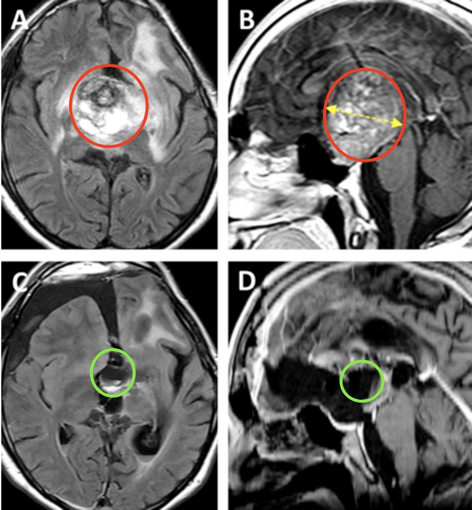

患儿4岁时,就曾因确诊丘脑毛细胞星形细胞瘤而接受开颅手术,手术并不彻底,因此术后他开始了两个周期的辅助化疗。然而,肿瘤在随后的12年内复发,患儿出现了全垂体功能减退和严重的左侧视力障碍,几乎等同于左眼失明。MRI显示鞍区-丘脑巨大肿瘤,侵犯累及左侧海马旁回和侧脑室的上部。肿瘤体积达68.1mm³,其深度为44.4mm(黄色虚线)。

根据患儿的病情、肿瘤生长及MRI影像特点,巴教授决定采用双冠状皮肤切口、双额骨瓣开颅、经基底纵裂入路进行肿瘤切除手术。术后MR提示肿瘤近全切除,从而使患儿的视交叉和视神经束、垂体柄和下丘脑保持原样,极大保障了孩子之后的生活质量。